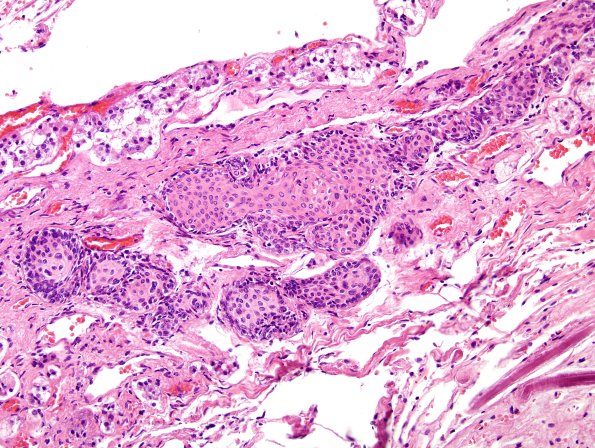

5C3 Pituitary stalk, squamous islands H&E 1

The stalk often contains squamous islands called “Erdheim rests”. (H&E)